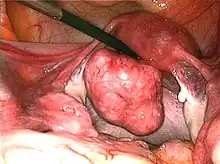

Uterine fibroids as seen during laparoscopic surgery